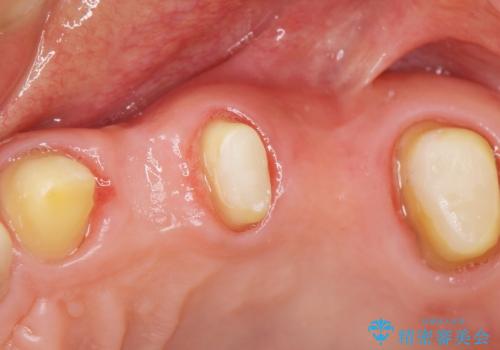

インプラント・ブリッジ・入れ歯の選択肢を提案させて頂いたところ、ブリッジをご希望されました。

保存不可能な歯(左上4)を抜去後、ブリッジによる補綴治療を行いました。

- ¥760,000 (根管治療×2本、土台×2本、仮歯×5本、クラウン×5本)費用は治療当時の料金となります